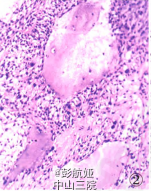

入院后行病理检查见右颈内静脉见癌栓,心脏扇扫显示左房占位,CT示肺内多数小点状阴影,考虑甲状腺癌转移,行左心房肿物切除术。术中见左房内肿物与房壁无关,肿物由肺静脉内长出,另见肺静脉内多发肿物。术中将左房内肿物送快速病理检查。眼观:肿物大小9 cm×7 om×5 cm,切面灰白色,黏液样,部分质韧,部分质软。镜检:黏液样物质背景下见肿瘤细胞呈梭形及圆形,呈团巢状、网格状排列,未见核分裂象。术中快速冷冻病理诊断:间叶源性肿瘤,部分区域细胞增生活跃,考虑肌源性可能性大。术后肿物行病理检查,镜下见肿瘤细胞呈梭形、圆形,细胞核较大,呈团巢状、网状排列,核分裂象少见,间质少,有大量粉染无结构物质,局部见大量坏死。免疫表型:vimentin、CK、TTF一1均(+++),Ki-67增殖指数<5%,Syn(灶状+),S-100、desmin、Myod.1、CR、HEMB一1、CKl9、SMA、p53、p63、Galectin-3、CK5/6、CK8/18、TG均(一),CT(+)(图4),刚果红染色:淀粉样物阳性

病理诊断:恶性肿瘤,结合病史及免疫表型考虑为甲状腺髓样癌转移癌栓。